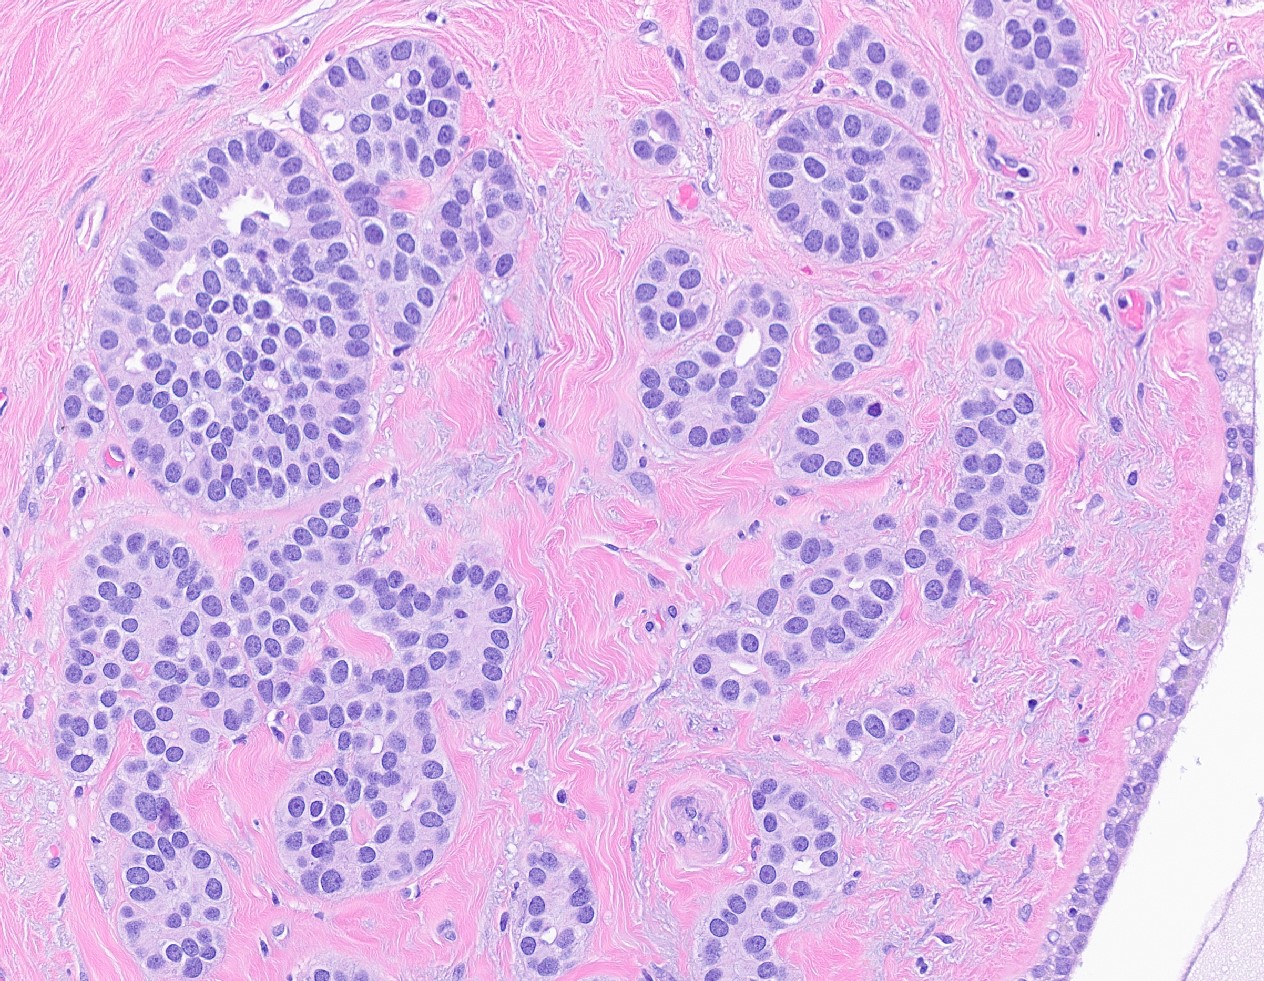

Microscopic (histologic) description

- Histologic grading is based on the Nottingham / modified Bloom & Richardson Score (Histopathology 1991;19:403):

- Tubule formation (1 - 3 points):

- > 75% (1 point)

- 10 - 75% (2 points)

- < 10% (3 points)

- Nuclear pleomorphism (1 - 3 points):

- Small, regular, uniform, similar to normal ductal epithelial cells, 2 - 3x RBC (1 point)

- Moderate increase in size / variability (2 points)

- Large nuclei, marked variation, often vesicular chromatin with prominent nucleoli (3 points)

- Mitotic count (1 - 3 points), dependent on microscopic field area

- Total score (add points for tubule formation, nuclear pleomorphism and mitotic count):

- 3 - 5 points: grade 1

- 6 - 7 points: grade 2

- 8 - 9 points: grade 3

- Histological features of IBC NST vary considerably from case to case and even within the same case

- Architecture varies from sheets, nests, clusters, cords or individual cells (but lacks the cytomorphological characteristics of invasive lobular carcinoma)

- Tubular formations are prominent in well differentiated tumors but absent in poorly differentiated tumors

- Variable cytological features:

- Cytoplasm may be abundant and eosinophilic but it can show other features in some tumors, including as clear, foamy or granular

- Nuclei may be regular and uniform or highly pleomorphic with prominent or multiple nucleoli

- Mitotic figures are variable from virtually absent to extensive

- 2 distinct growth patterns exist:

- Large and solid nests or syncytial infiltrative growth pattern with little associated stroma and an expansive growth that compresses the surrounding stroma (e.g., most basal-like breast cancers)

- Tumors characterized by small cancer nests accompanied by marked fibrosis (desmoplastic / scirrhous); this type diffusely infiltrates the surrounding tissue as an irregular shaped spiculated mass

Microscopic (histologic) images

Contributed by Julie M. Jorns, M.D., Kristen E. Muller, D.O., Gary Tozbikian, M.D. and Emad Rakha, M.D.